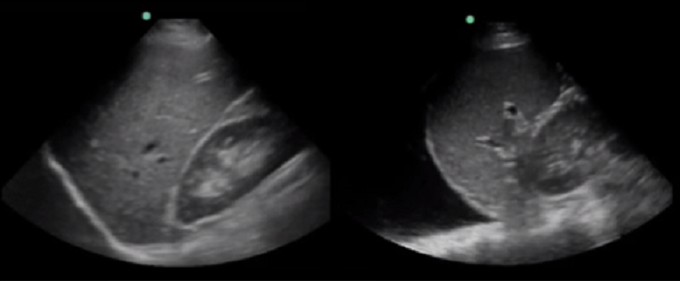

RUSH Abdominal Fluid Yes/No Comparison Image